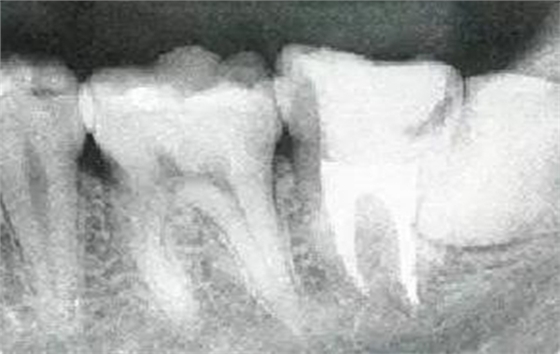

參考病例① 35歲女性

在左下第一磨牙在25歲時(shí)近中處可以看到垂直性的骨吸收,但35歲時(shí)吸收停止,原本沒(méi)有見(jiàn)到的遠(yuǎn)中處骨吸收的,現(xiàn)在卻吸收得很?chē)?yán)重。

在右下處,原本有大量骨吸收的第一磨牙處的吸收卻變緩慢,原本沒(méi)有吸收的第二前磨牙卻出現(xiàn)了吸收。出現(xiàn)吸收的左上第一磨牙的遠(yuǎn)中處,吸收得越來(lái)越多了。

把10年間的變化做成表格。牙周病的發(fā)展根據(jù)各個(gè)人會(huì)不同,即使通一個(gè)人,不同牙齒,不同牙面發(fā)展的狀態(tài)也不同。